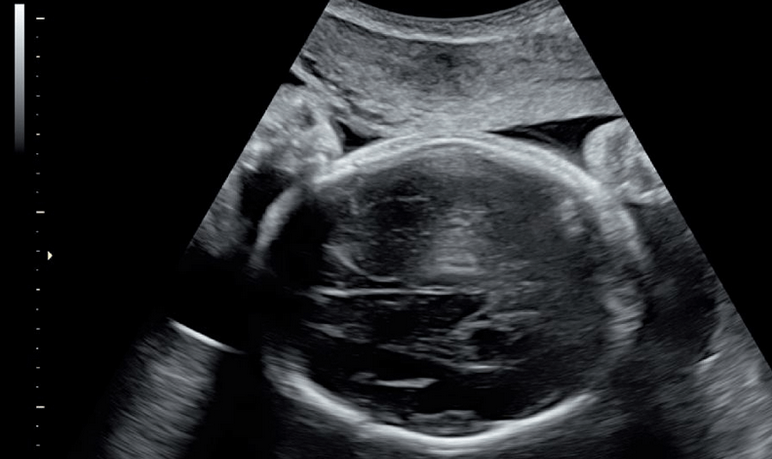

药流怎么判断孕囊排出图片(药流的最佳时间是多少天做)

其实,药流流干净的几率在80%左右,但是具体的几率因人而异。在现今社会,药流的女性比率在逐渐升高,微博上一个帖子讲述了一个女性药流了肚子里60天孕周的孩子,而图片就是孩子的照片。

其实最好的时间是小于妊娠49天的,这个只是个大概值,要是我们将药物流产的最佳时间精确到怀孕的具体时间的话,是在怀孕后的三十五天到四十五天之间。最佳时间之所以在那个时候原因是此时孕囊发育的时间还不是很长,孕囊本身的体积还不是很大,而子宫腔里面的孕囊和妊娠组织也还不是很多,所以说药物流产的难度小,因此药流的成功率高,出现药流不完全的概率会降低。所以说要是怀孕天数处在这个时期的话,做药物流产无疑是最好不过的。